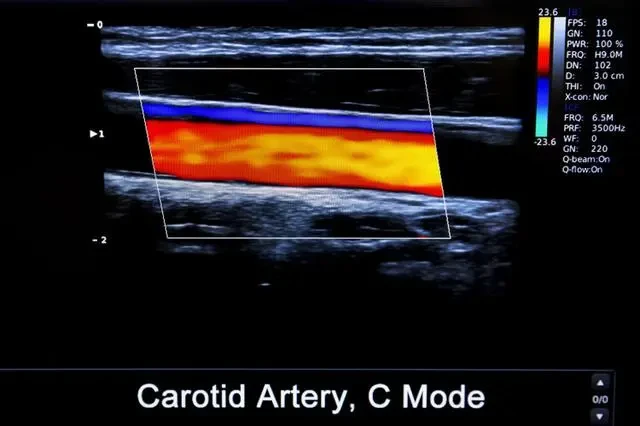

3、血管鈣化

這個問題在老年人身上相對常見,是指血管壁上出現了堅硬的鈣化物,在動脈上較為常見。老年人罹患三高、長期吸煙以及久坐等因素,都容易引起鈣化,嚴重的會誘發心肌缺血、心力衰竭。